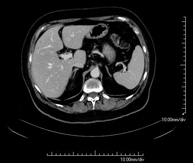

- TC Abdomen

Prova diagnòstica que consisteix en l'estudi de l'abdomen d'alta definició anatòmica (fetge, vesícula biliar, via biliar, pàncrees, melsa, estómac, intestins, ronyons, estructures vasculars, bufeta, úter i ovaris, etc.) mitjançant l'ús d'un equip de TC (Tomografia Computeritzada). Aquestes imatges s'estudien posteriorment en una estació de treball que permet obtenir reconstruccions bidimensionals en diferents plànols de l'espai i també reconstruccions 3D (volumètriques). La majoria d'estudis requereixen l'ús de contrast iodat per millorar la definició de les imatges. - TC Pelvis